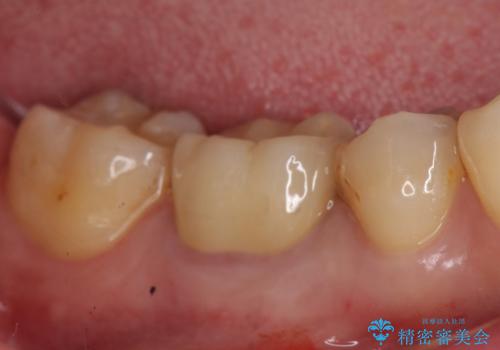

金属の奥歯 → 白い奥歯 根管治療からのやり直し

- 再根管治療→土台の築造 を行った上でのかぶせ物のやり替えをおこないました。

かぶせ物の種類:Bellezza